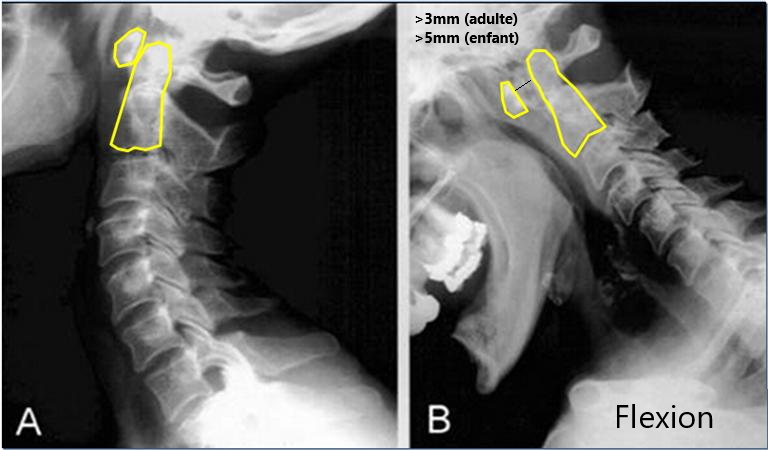

- Distance dent-C1 en Flexion >3mm (>5mm enfant)